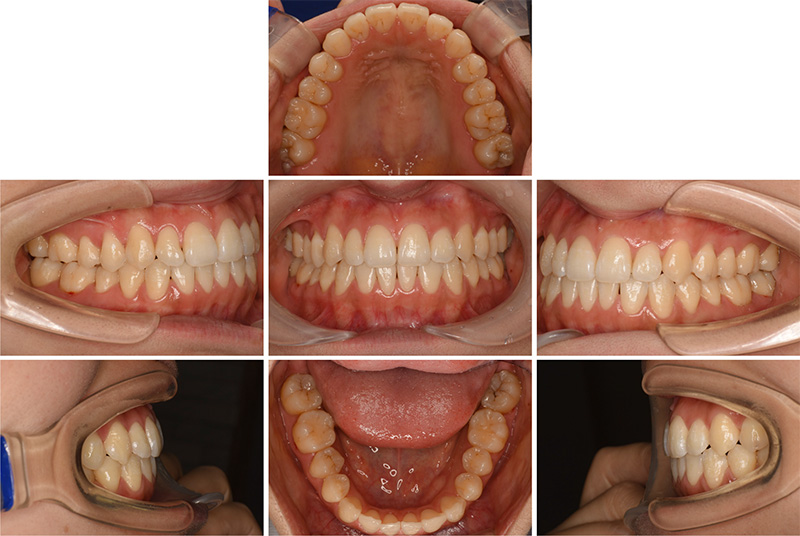

46歳女性

治療後

| 施術名 | インプラント治療 |

| 施術の説明 | インプラント治療とは、歯を抜いた所にチタン製の人工歯根を埋入し、新しく歯を入れる方法です。 |

| 施術の副作用 (リスク) | 腫れや疼痛を感じる、違和感を感じるなどの症状を生じることがあります。 |

| 施術の価格 | 53万円~+消費税 |